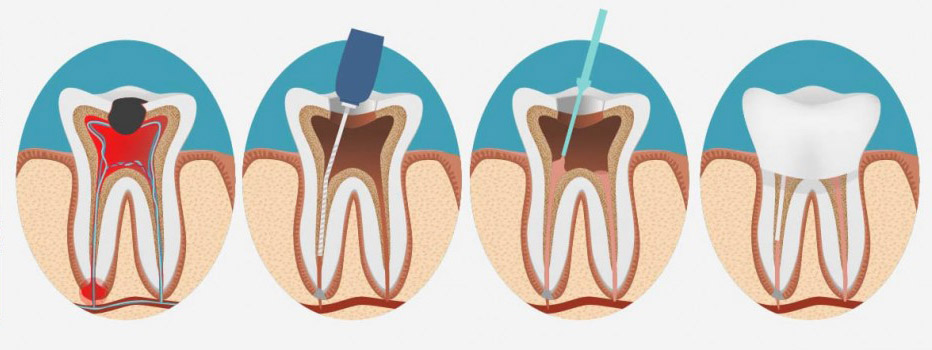

درمان ریشه دندان به معنای خارج کردن عصب یک دندان، تمیز کردن و شکل دادن به فضای کانال است و در آخر نیز جهت ممانعت از ورود میکروب و باکتری به عصب دندان باید دندان را پر کنند. درمان ریشه دندان به این جهت انجام می شود که دندان را هر چند بدون عصب زنده داخل دهان داشته باشیم و در کنار آن نیز در زمان خوردن درد نداشته باشیم. دندانپزشک متخصص در کلینیک دندانپزشکی تریدنتال می تواند بهترین خدمات را در این زمینه به شما ارائه دهد. همچنین باقی ماندن دندان داخل دهان باعث حفظ زیبایی و ظاهر بیمار نیز می گردد. درمان ریشه دندان معمولاً نیازمند یک یا دو جلسه ملاقات با پزشک می باشد، اما در بعضی موارد ممکن است به علت سختی کار یک جلسه دیگر نیز به دوره درمان ریشه دندان اضافه شود.

در این روش پس از حذف پالپ ناحیه تاجی و ریشه ای، به منظور کامل کردن فرایند درمان ریشه دندان، چند اقدام دیگر را انجام می دهد. وی با استفاده از وسایل تخصصی ویژه، فرایند تمیز کردن و عاری کردن داخل کانال های ریشه دندان از محتویات را انجام داده به نحوی که در پایان این مرحله اطمینان می یابد که کانال عصبی کاملا تمیز و عاری از هر گونه آلودگی است. وی برای انجام این کار بارها پس از عمل ساییدن دیواره های کانال، با کمک سرم فیزیولوژی اقدام به شستشو مکرر نموده و قطعات جدا شده حین عمل سایش را خارج می نماید.

اقدام بعدی اندودنتیست، فرم دهی و شکل دهی کانال تمیز شده است تا با ایجاد شکلی مناسب به این فضا امکان پر کردن یکنواخت و همگن کانال مهیا شود. در تکمیل فرایند درمان ریشه، مرحله پر کردن فضای تمیز و فرم داده شده است که برای انجام این فرایند از ماده ای که از یک صمغ طبیعی تهیه گردیده است بنام “گوتاپرکا” استفاده می شود. این کار به شکلی انجام می شود که این ماده تمامی فضای کوچک و ظریف کانال ریشه دندان را پر کند به شکلی که هیچ گونه حباب یا منفذی برای نشت مواد به داخل کانال مقدور نباشد.

در پایان متخصص درمان ریشه، با گذاشتن ماده ای موقت به صورت پانسمان در ناحیه تاجی ضمن مسدود کردن فضای تاجی دندان و جلوگیری از نشت بزاق و میکروب به فضای کانال های درمان شده، بیمار را برای ترمیم ناحیه تاج به متخصص دندانپزشک ترمیمی در تهران و یا پروتزهای دندانی ارجاع می دهد.